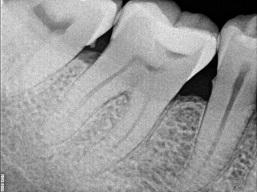

Kui pulpiiti õigel ajal ei ravita, tekib hamba juureümbrise põletik ehk periodontiit. Ka see võib kulgeda ägedalt (valuga) või krooniliselt (valutult). Enamasti on selles etapis võimalik ka juba röntgenpildilt näha muutusi hammast ümbritsevas luukoes.

võib kulgeda ilma sümptomiteta, ilma valuta. Aeg-ajalt võib tekkida igemele hamba juuretipu piirkonda fistel, millest eritub veidi mäda. Juureümbrise põletikku on võimalik diagnoosida röntgenpildilt. Seal on näha muutused juuretippu ümbritsevas koes. Selline hammas vajab kindlasti ravi, hoolimata sellest, et ta ei põhjusta sümptomeid.

Krooniline periodontiit